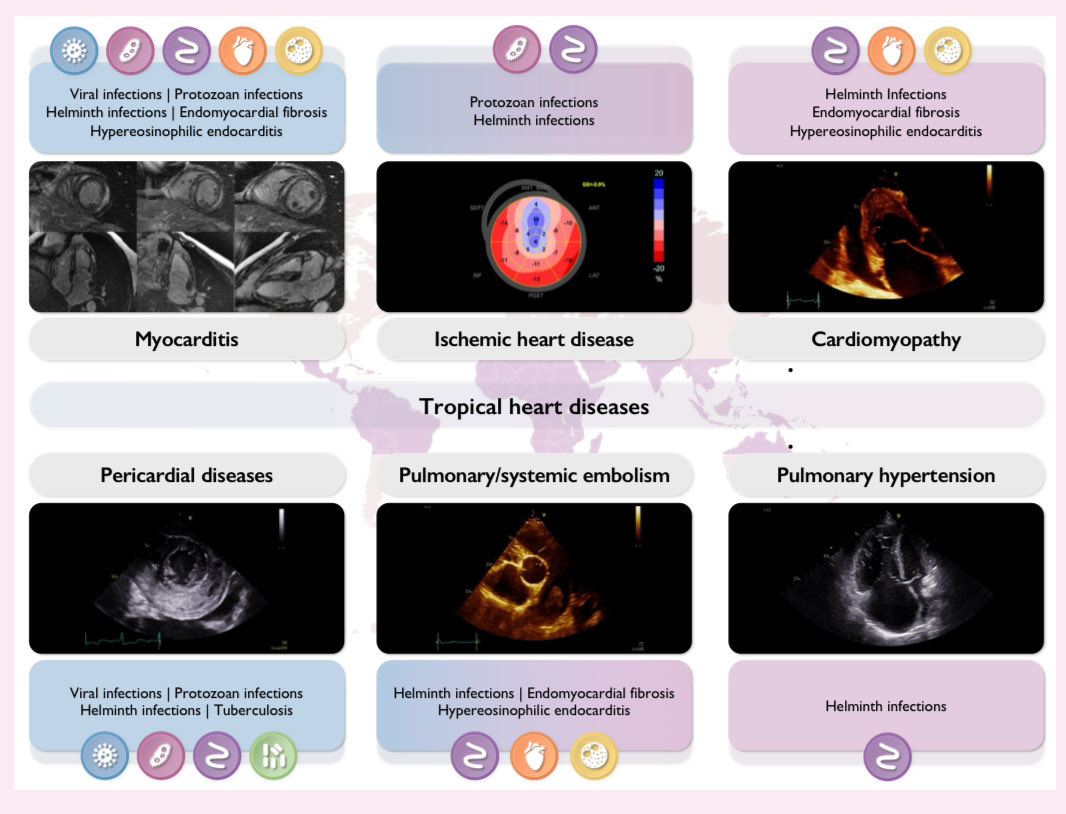

🗺️ Cardiac imaging in patients with tropical diseases: a scientific statement @ESC_Journals #Cardiology #CardioEd #echofirst #FOAMed

🗺️ Cardiac imaging in patients with tropical diseases: a scientific statement @ESC_Journals #Cardiology #CardioEd #echofirst #FOAMed